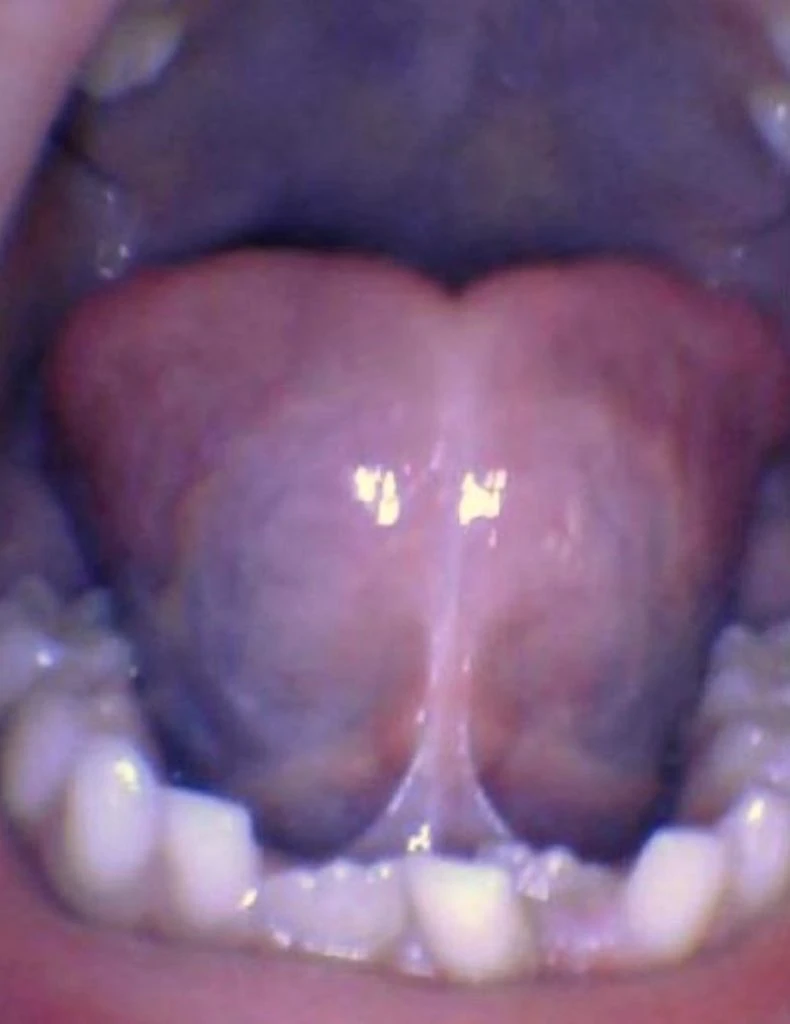

These images show the spectrum of tongue restriction in an infant.

View tongue restrictions

These images show the spectrum of tongue restriction in a child.